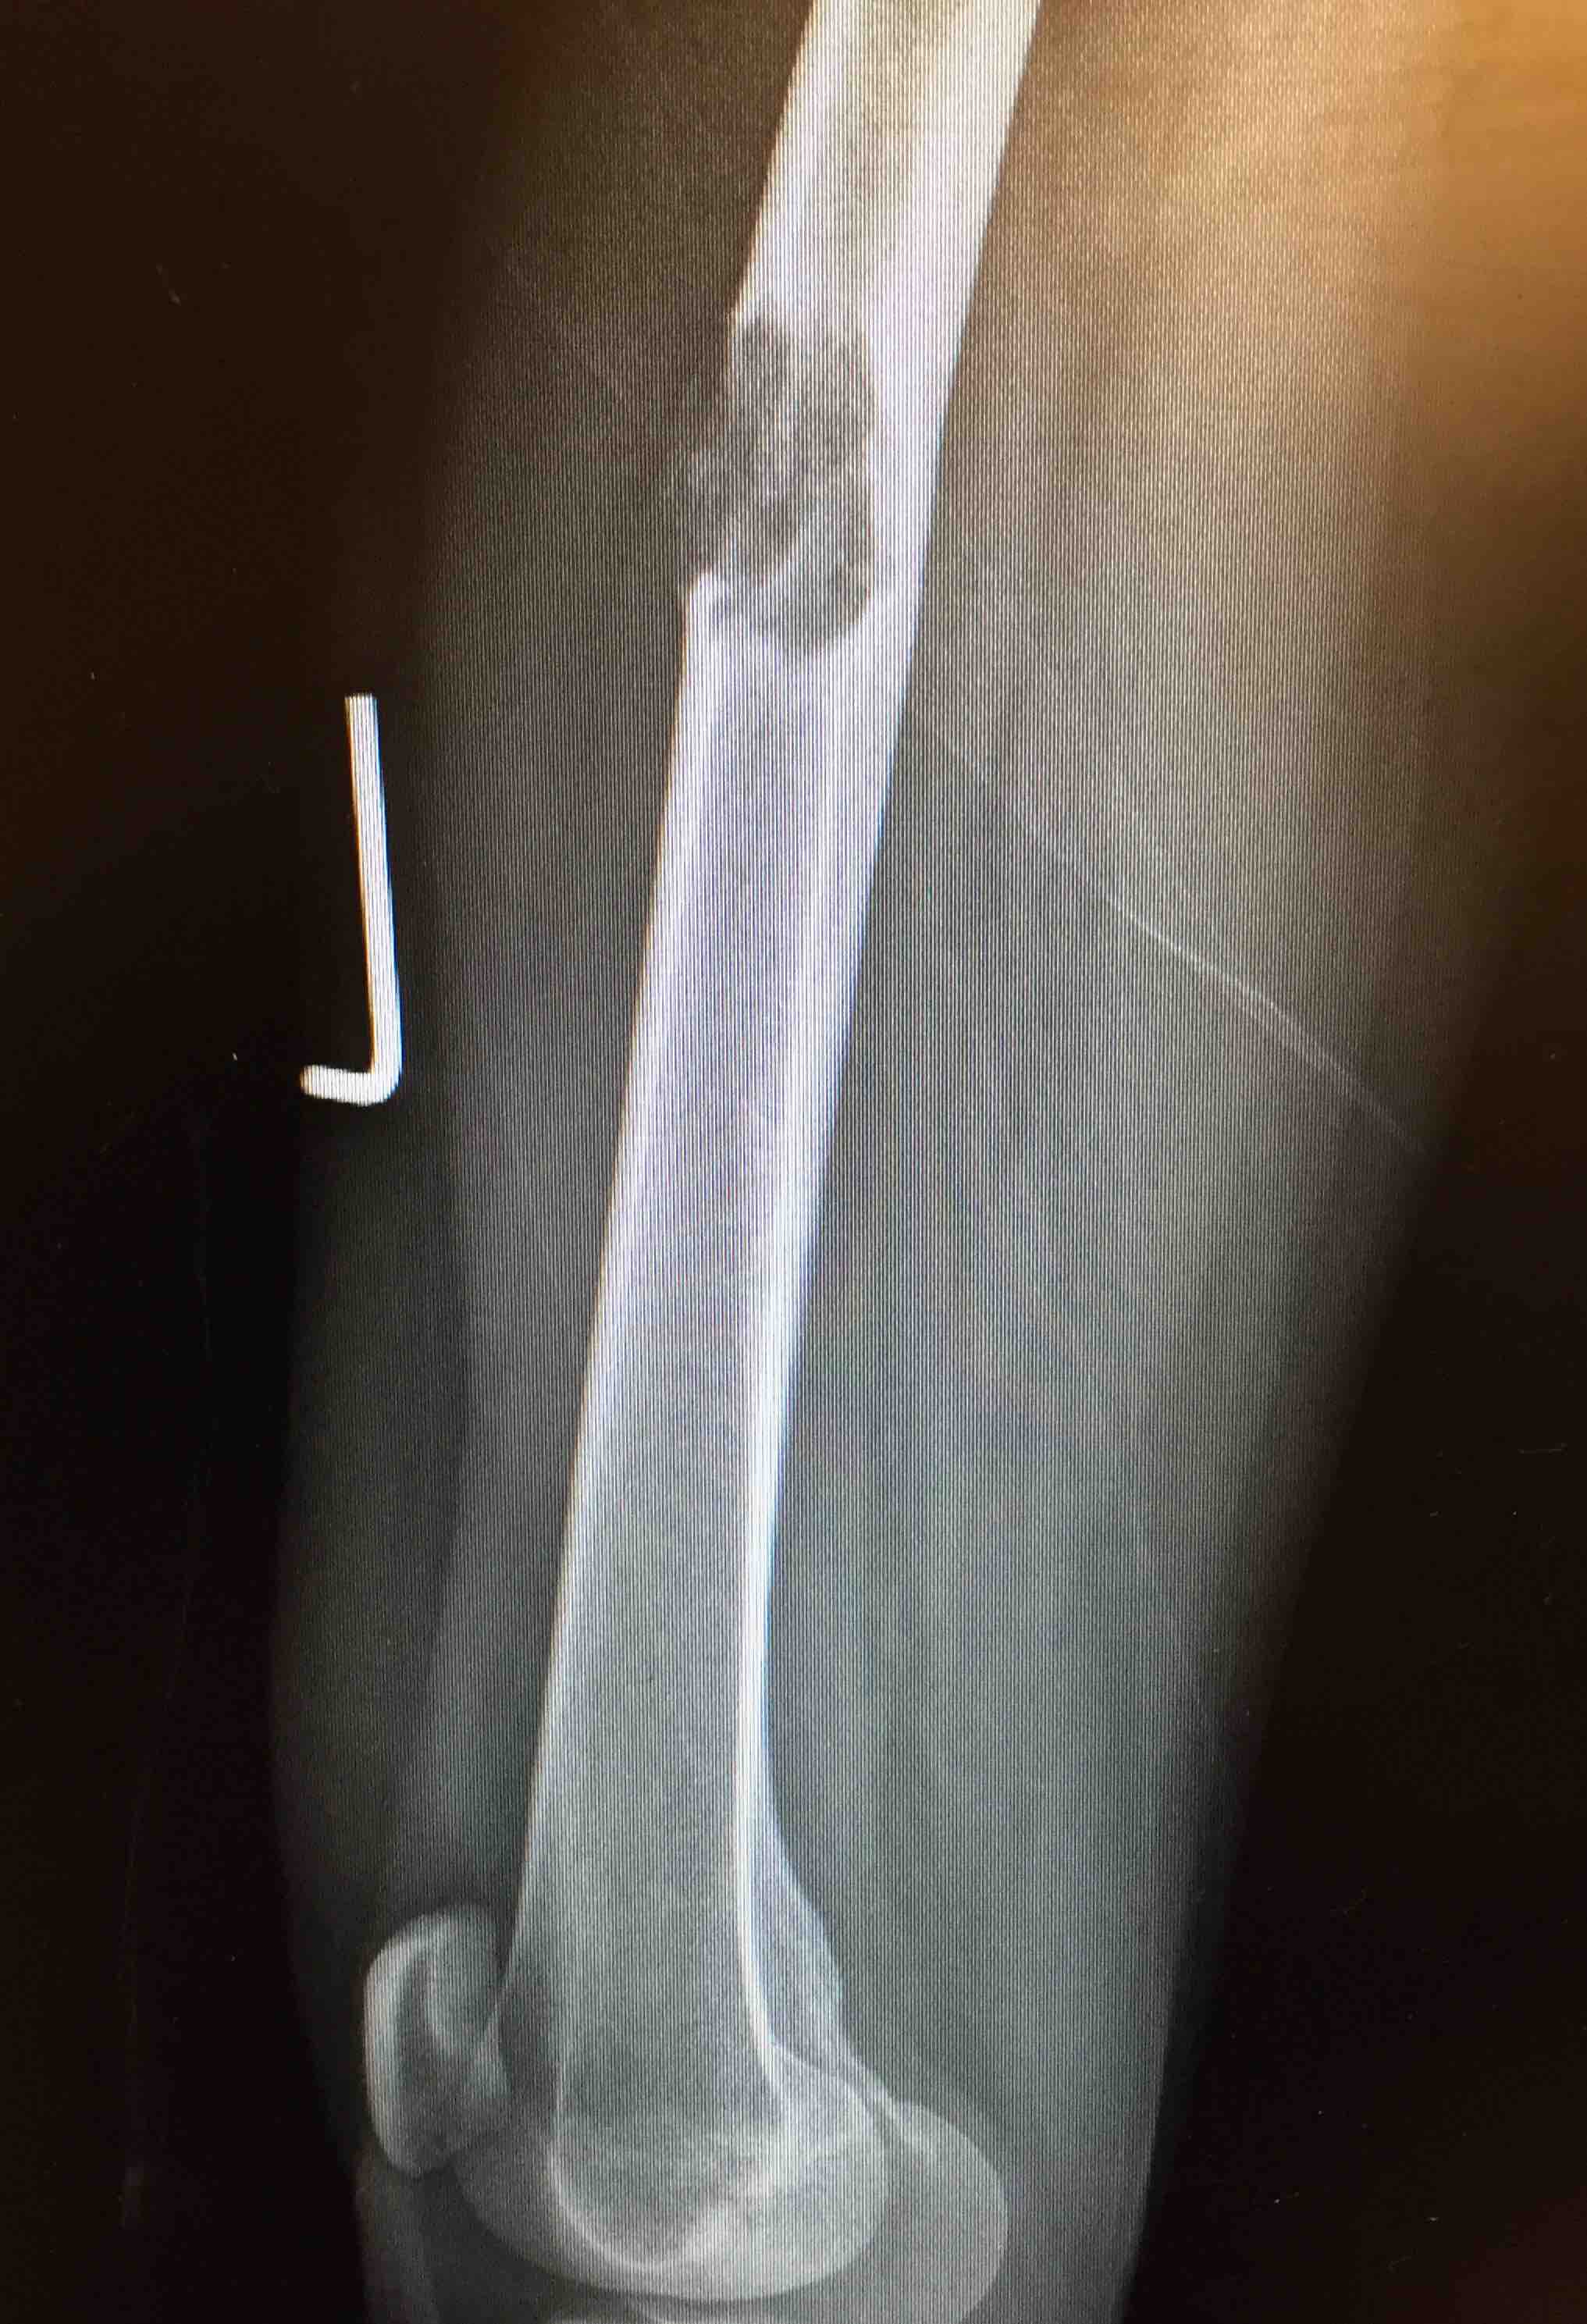

Background

Aim

The identification of skeletal metastasis & fixation prior to fracture

Incidence

50% of new cancer cases have metastasis

- 1% have pathological fracture

- increasing with more aggressive palliative care